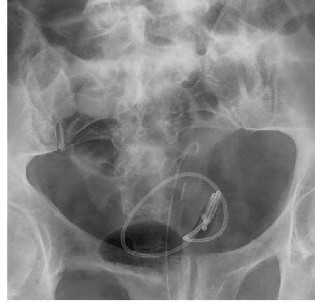

Vôi hóa ống thông niệu quản JJ

Các yếu tố khác nhau như nước tiểu quá bão hòa, mang thai, mang ống thông niệu quản thời gian dài… làm tăng nguy cơ vôi hóa bề mặt thông niệu quản [116].

Theo báo cáo của el-Faqih S.R. và cs (1991) [50] thì tỷ lệ vôi hóa ống thông niệu quản là 9,2% (đặt < 6 tuần), 47% (đặt 6 – 12 tuần) và khoảng 76,3% (đặt > 12 tuần). Theo báo cáo khác của tác giả Kawahara T. và cs (2012) [89] thì tỷ lệ vôi hóa ống thông niệu quản là 26,8% (< 6 tuần), 56,9% (6 -12 tuần) và khoảng 75,9% ( > 12 tuần). Sự vôi hóa có thể gặp ở đầu xa của ống thông nằm trong bàng quang, dọc theo chiều dài ống thông nằm trong niệu quản hoặc đầu gần của thông trong bể thận.

Hình 1.14. Ống thông niệu quản JJ vôi hóa trên phim hệ tiết niệu không chuẩn bị và nội soi bàng quang

(Nguồn: Aboutaleb HA, 2019) [15]